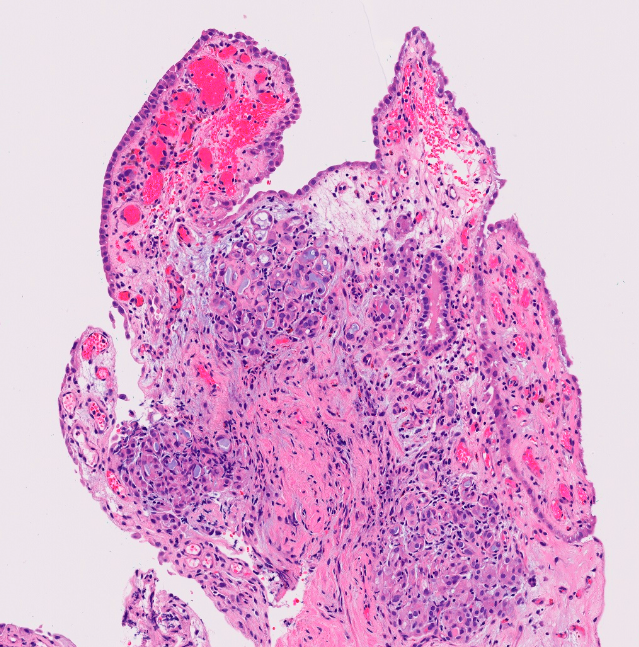

Dx:

Key histo features:

Lichen sclerosis

Normal to atrophic epithelium covering a band of diffuse sclerosis in the lamina propia overlying a dense and continuous band of lymphocytes. Note the vacuolization of basal cells and the globular perivascular hyalinization at the epithelial-stromal interface.